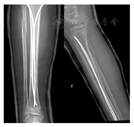

选择直径为胫骨髓腔最窄直径三分之一的弹性髓内钉,将其预弯,使最凸面达到骨折水平,弧度为髓腔直径的3~5倍。在患肢胫骨结节水平两侧做1~2 cm小切口,钝性分离直达骨膜,切开骨膜,骨锥斜形钻孔,分别拧入2枚髓内钉,透视定位髓内钉达骨折线水平时,术者与助手牵引下闭合复位,术者一手维持牵引,一手继续拧入髓内钉过骨折线,达远端胫骨骨骺上方约1 cm,使两枚髓内钉"X"形交叉,弧顶位于骨折断端,形成3点固定(图4)。

一般无需手术治疗,在胫骨复位后,腓骨对位对线均有明显改善(图4)。

4例患儿胫骨下段骨折对位对线良好,采取石膏固定保守治疗;5例患儿采取手术治疗固定胫骨(4例采取弹性髓内钉固定,1例采取弹性髓内钉联合克氏针固定),伤后至手术时间平均5.9 d,腓骨骨折均仅行石膏外固定制动。采取手术治疗固定胫骨的5例患儿,胫骨复位后腓骨骨折分离及短缩移位程度均有明显改善,术前腓骨骨折平均短缩7.9 mm,术后为3.1 mm;术前腓骨骨折平均分离8.5 mm,术后为3.3 mm。